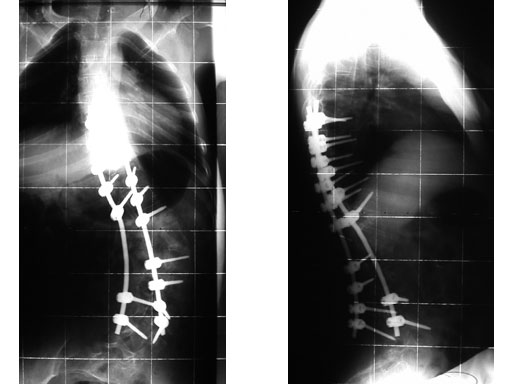

Case provided by Cornelius Wimmer, Vogtareuth, Germany

A 23-year-old man with neurogenic kyphoscoliosis, Cobb angle: 120. Fusion of T7S1 with universal reduction screws. Duration of surgery: 4.5 hours.